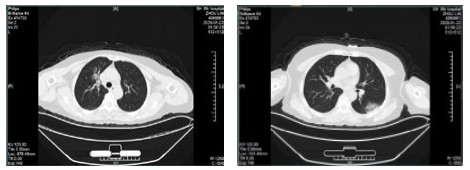

| 图 2 患者,女性,64岁,武汉籍,发病前1 d由武汉自驾车入沪,出现发热,体温39.9℃, 伴全身乏力,无咳嗽症状,无鼻塞,流涕症状,血白细胞总数及淋巴计数正常,甲乙型流感病毒筛查阴性,新型冠状病毒核酸检测阳性,肺部CT双肺多发磨玻璃结节,部分贴近胸膜,左肺有少量胸腔积液,局部小叶间隔增厚, 可见纤维条索影 Fig 2 Case 2, female, 64 years old, born in Wuhan. One day before the onset of the disease, she drove into Shanghai from Wuhan and had fever. Her body temperature was 39.9℃, with general asthenia, no cough, no nasal obstruction and running nose, normal WBC and lymphoid count, negative influenza A and B virus screening, positive novel coronavirus nucleic acid test. Lung CT showed multiple ground glass nodules, some of which were close to pleura, a small amount of pleural effusion in the left lung, and local interlobular septa was thickened, with visible fibrous streak shadow |

| 图 3 患者,女性,49岁,沪籍,发热10 d,体温最高38.5℃,伴乏力,肌肉酸痛,既往体健。否认武汉流行病学接触史,有菜场买菜史。血白细胞总数及淋巴计数正常,甲型、乙型流感筛查阴性,新型冠状病毒核酸检测阳性。肺部CT提示双肺磨玻璃结节,可见血管充血,增粗,穿行,部分贴近胸膜,伴小叶间隔增厚 Fig 3 Case 3, female, 49 years old, born in Shanghai, had fever for 10 days, body temperature 38.5℃, with fatigue, muscle pain, previous physical fitness. She denied the history of epidemic exposure of Wuhan, but had the history of shopping in market. Normal WBC and lymphoid count, negative influenza A and B virus screening, positive novel coronavirus nucleic acid test. Lung CT showed bilateral ground glass nodules with hyperemia, thickening and passage of blood vessels. Some were close to pleura with thickening of interlobular septum |

| 图 4 患者,男性,59岁,湖北籍,春节回乡探亲返沪,发热2 d入院,体温37.8℃, 乏力,既往体健。血白细胞总数及淋巴计数正常,甲型、乙型流感筛查阴性,新型冠状病毒核酸检测阳性。肺部CT提示双肺多发磨玻璃结节,病灶贴近胸膜伴支气管充气征及血管充血、增粗,可见部分纤维条索影 Fig 4 Case 4, male, 59 years old, born in Hubei Province, returned to Shanghai during the Spring Festival. He was hospitalized 2 days after fever, with a body temperature of 37.8℃ with fatigue. Normal WBC and lymphoid count, negative influenza A and B virus screening, positive novel coronavirus nucleic acid test. Lung CT showed multiple ground glass nodules in both lungs. The focus was close to the pleura, accompanied by bronchiectasis, hyperemia and thickening of blood vessels. Some fibrous bands could be seen |